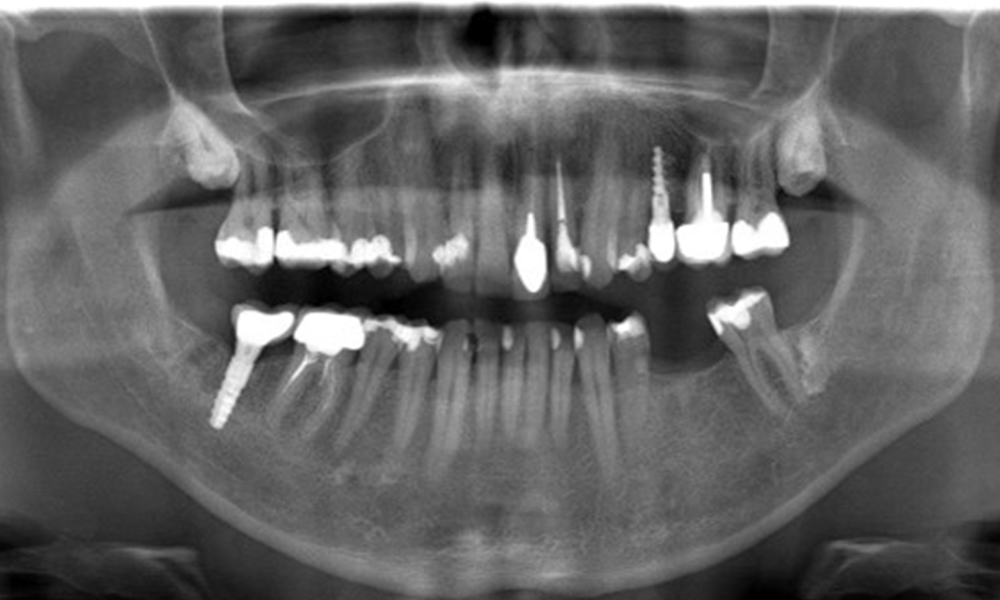

In the medical history, the 55-year-old patient states that he has no systemic disease and is not taking any medication. The patient’s lifestyle is similarly unremarkable. The patient has a few tooth restorations and two implants (2nd and 4th quadrants). On the basis of current findings, gingivitis is identified in an otherwise stable periodontal condition on the reduced periodontium (stage III, grade A).

Previous treatments: dental restorations (non-precious metal/ceramic blend), two implants (2nd, 4th quadrants)

The patient has no particular risk factors with specific dental implications. The key factor, therefore, is the requirement in terms of oral health. In this respect, good oral health is evident with stable, reduced periodontium. Should evidence of an increase in probe depth compared with the baseline, combined with diffuse bleeding, be found at a check-up appointment, diagnosis using X-ray imaging (dental X-ray) should be undertaken in order to identify peri-implant bone loss at an early stage and intervene accordingly.

On the basis of the stable periodontal and peri-implant situation, it is recommended that the patient should have check-ups every six months.